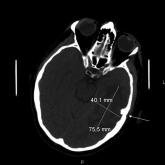

Malignant Otitis Externa